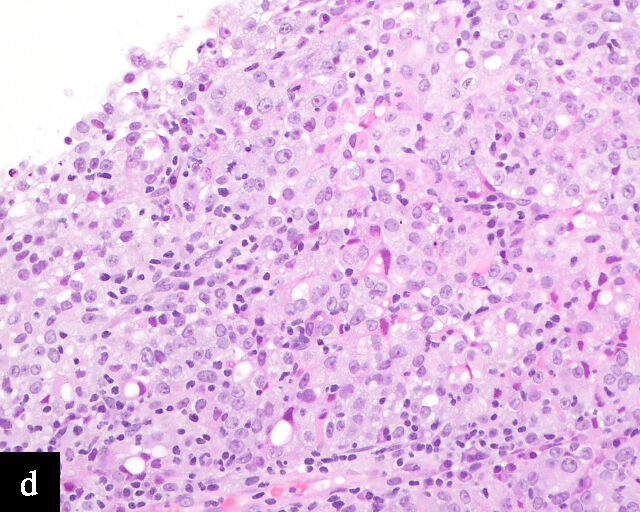

2

Histological sections of HPV-independent cervical carcinomas. (a) Clear cell adenocarcinoma. (b) Endometrioid adenocarcinoma. (c) Well-differentiated gastric-type adenocarcinoma. (d) Poorly differentiated gastric-type adenocarcinoma. H&E stain. Magnification ×20.

Clear cell adenocarcinomas of the cervix follow a bimodal age distribution. The first peak is observed at late adolescence/early adulthood13,14 and is associated with in-utero exposure to diethylstilbestrol (DES). The median age at presentation for clear cell adenocarcinoma not related to DES exposure is 48 years15 and constitutes the second peak. Its histological appearance resembles that of clear cell adenocarcinomas from other parts of the female genital tract (uterine corpus and ovaries), in particular tumor cells displaying overt nuclear atypia and a characteristic clear cytoplasm, arranged in variable destructive growth patterns16 (Figure 2a). Clear cell adenocarcinomas of the cervix share common immunophenotypic features with upper female genital tract carcinomas, notably PAX8 positivity and non-diffuse p16 expression17 (Figure 3a,b). Limited data from case series indicate that mutations in CMTM5 and WWTR1 are relatively frequently detected in clear cell adenocarcinomas of the cervix.18,19

Gastric-type adenocarcinomas frequently present at a late stage (parametrial involvement, ovarian and lymph node metastasis) with unfavorable histopathological features (lymphovascular invasion and positive peritoneal cytology) and significantly worse disease-free and overall survival compared to HPV-associated endocervical adenocarcinomas.24 Macroscopically, these tumors have been associated with a ‘barrel-shaped’ cervix, attributed to deep invasion and induction of desmoplasia, leading to diffuse enlargement and thickening of the cervix.25 The histological appearance of these tumors is diverse. Well-differentiated forms (Figure 2c) can be difficult to distinguish from non-lesional cervical glands, which is reflected in the older terminology ‘adenoma malignum’ and ‘minimal deviation adenocarcinoma’. These historically referred to gastric-type adenocarcinomas that exhibit bland morphological features.22 In contract, poorly differentiated tumors can display variable architectural patterns, ranging from irregular incomplete, glands to solid nests or single cells in which glandular differentiation is not readily evident26 (Figure 2d).